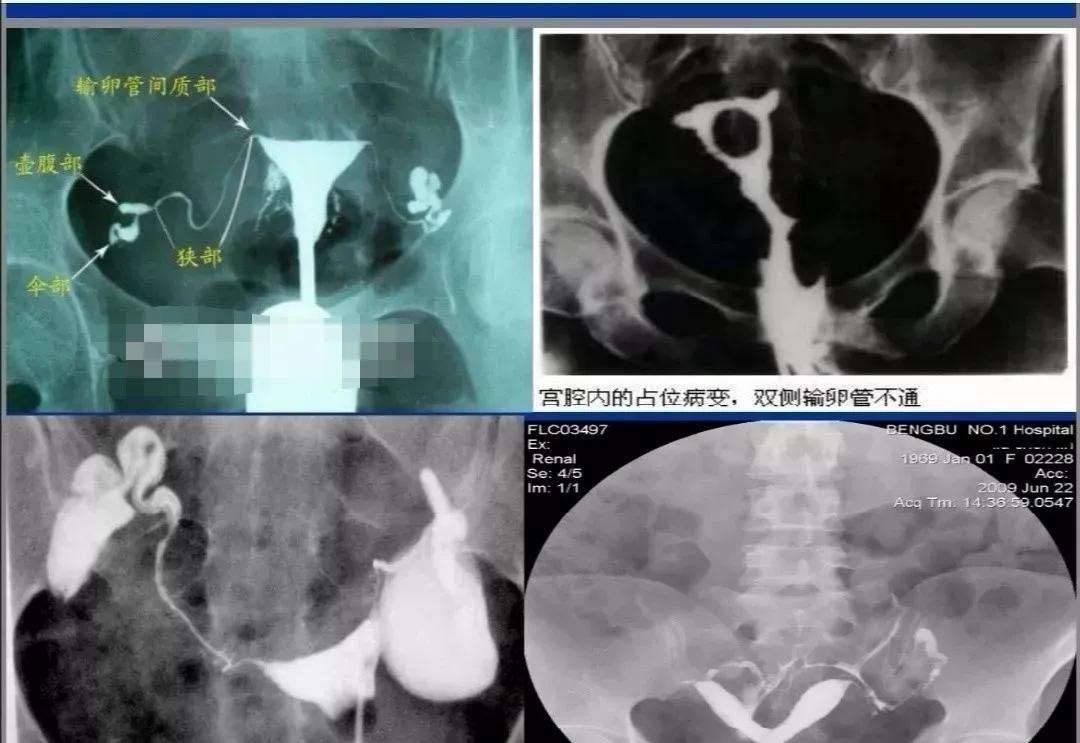

女性不孕中大约有25%~35%为输卵管性不孕,可由感染、子宫内膜异位症、盆腔手术创伤等引起。输卵管主要是起“传输”作用,传输精子、卵子、受精卵。据临床统计,输卵管疾病大概占女性不孕因素的25%~35%。

1、传统×线下子宫输卵管造影,检查费用多数在800-1000元;另外和造影剂的费用也是密切相关的,有的造影剂较贵,有的较便宜,手术费用在500-800元左右。

2、超声下子宫输卵管造影,这是近几年比较容易被大众接受的检查方法,好处是没有放射线的辐射,造影剂分解成气泡排出体外,没有直接作用;最大的优点是检查后一个月就可以备孕,所以超声造影现在更受到大家的欢迎。超声造影的手术费大约在1000-1500元,造影剂是500元,造影之前需要常规妇科检查、白带常规检查、传染病标志物检查、阴道准备和辅助用药等,所以超声造影需要花1500元左右。

3、检查输卵管的方法还有输卵管通液术,分为普通输卵管通液、B超监视下通液和宫腔镜插管通液。普通输卵管通液相对来说比较盲目,不推荐用于输卵管通畅度的评估,该检查费用比较低廉,大多数花费在300-500元左右,B超监视下通液大概费用1000-2000元左右,宫腔镜插管通液费用大概2000-3000元不等,如合并宫腔其他病变处理如黏连、息肉、导丝介入疏通治疗等费用6000-8000元不等。

4、腹腔镜微创手术,如果是单纯用于评估输卵管是否通畅有点大材小用,因为该项目花费较大,大约10000-20000元。如果只用于评估输卵管是否通畅,建议做超声下的子宫输卵管造影,超声造影是在四维情况下全方位观察子宫和输卵管形状、走形以及输卵管是否通畅。